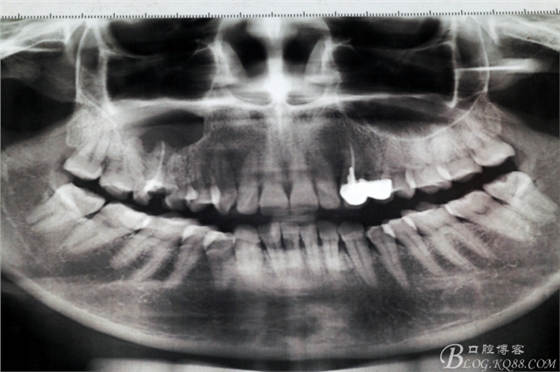

圖4.全景片影像檢查:以16為中心的橢圓形陰影,當時15未作根管治療。